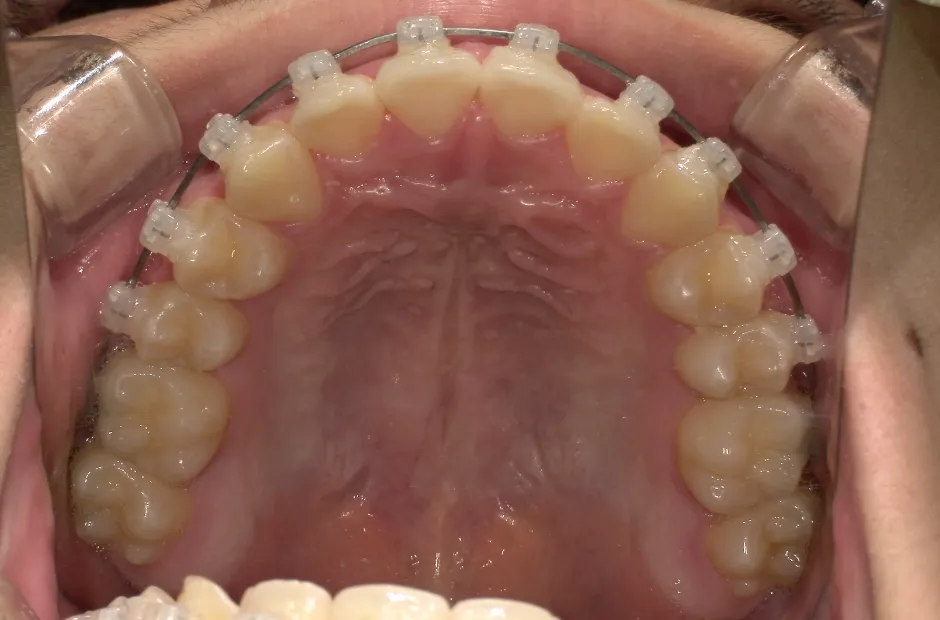

リンガルアーチ

| 診断名・主訴 | 反対咬合 |

|---|---|

| 年齢・性別 | 14歳・女性 |

| 治療期間・回数 | 2年6か月 |

| 治療に用いた主な装置 | リンガル |

| 抜歯部位 | 上顎5,5 下顎4,4 |

| 治療費 | 100万円(税抜) |

| リスク・副作用 | 装置による違和感・疼痛・歯肉退縮・歯根吸収・虫歯のリスクなど |

治療中